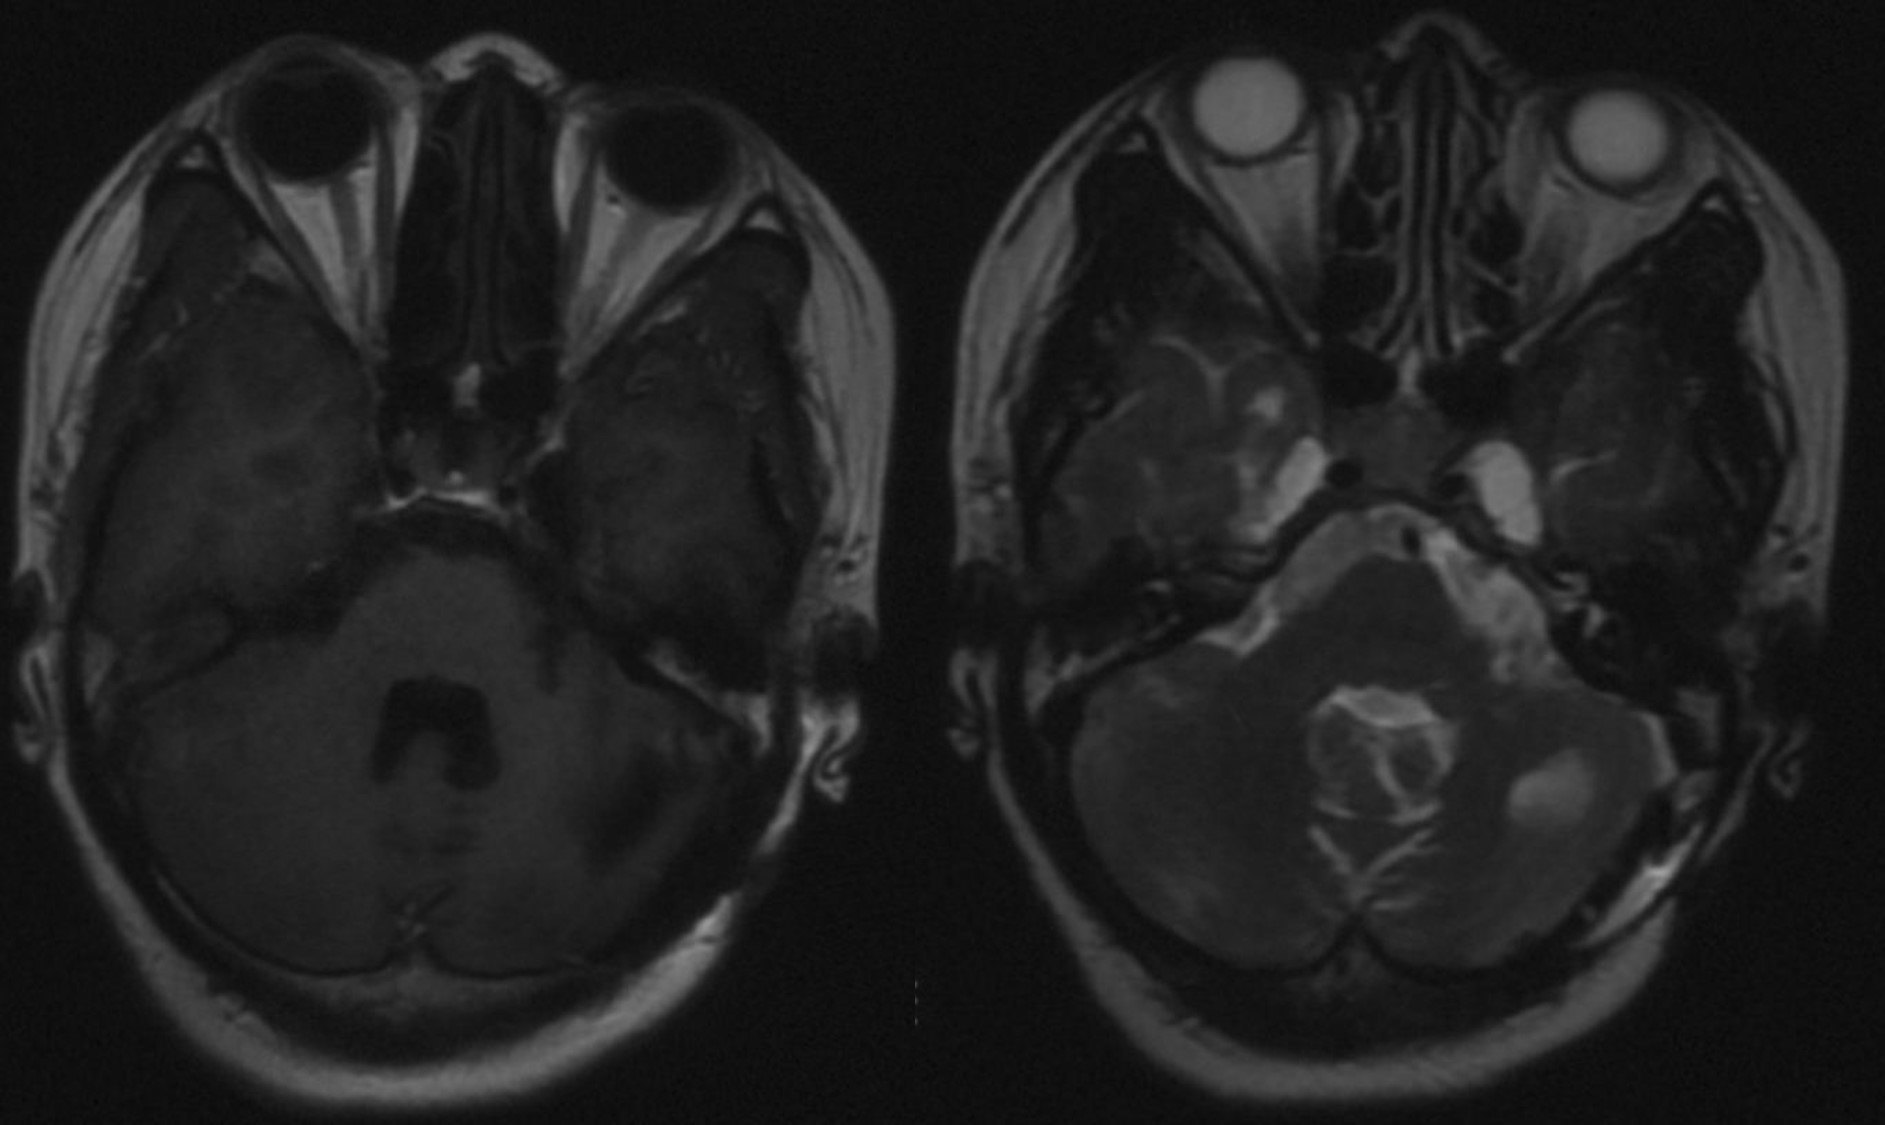

术后随访头颅MRI。